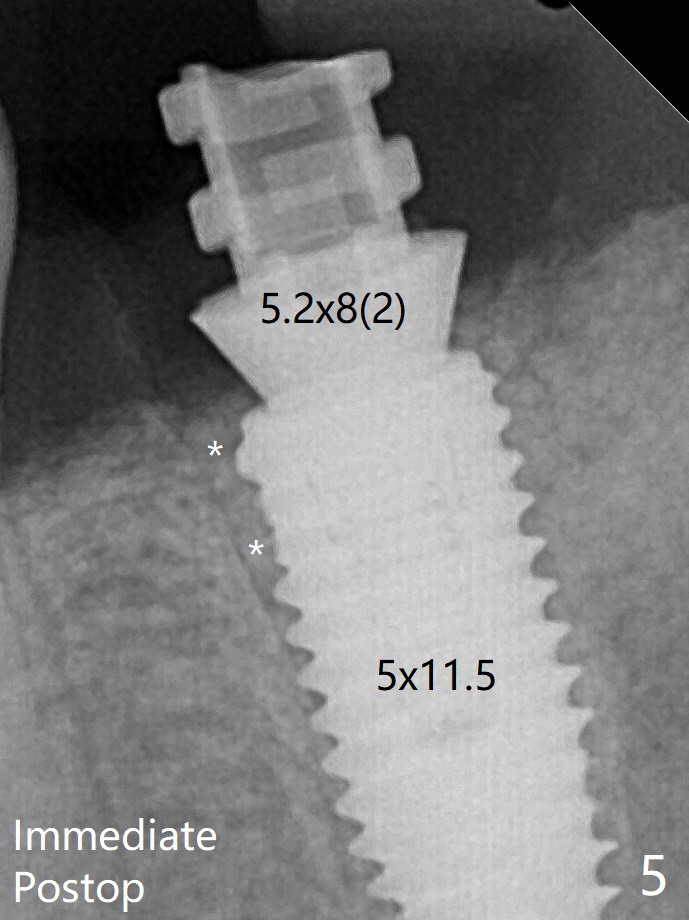

术后即刻近中牙槽窝间隙由粘性骨粉充填(图五:*(5.2x8(2)毫米临时基台)),四个月后间隙消失(硬骨板也消失,图七),5.2x5(3)毫米粘固基台似乎没有完全就位,可能因为远中牙槽嵴阻挡(图七:*)。可以使用profile drill,但是必须打麻药,出血。